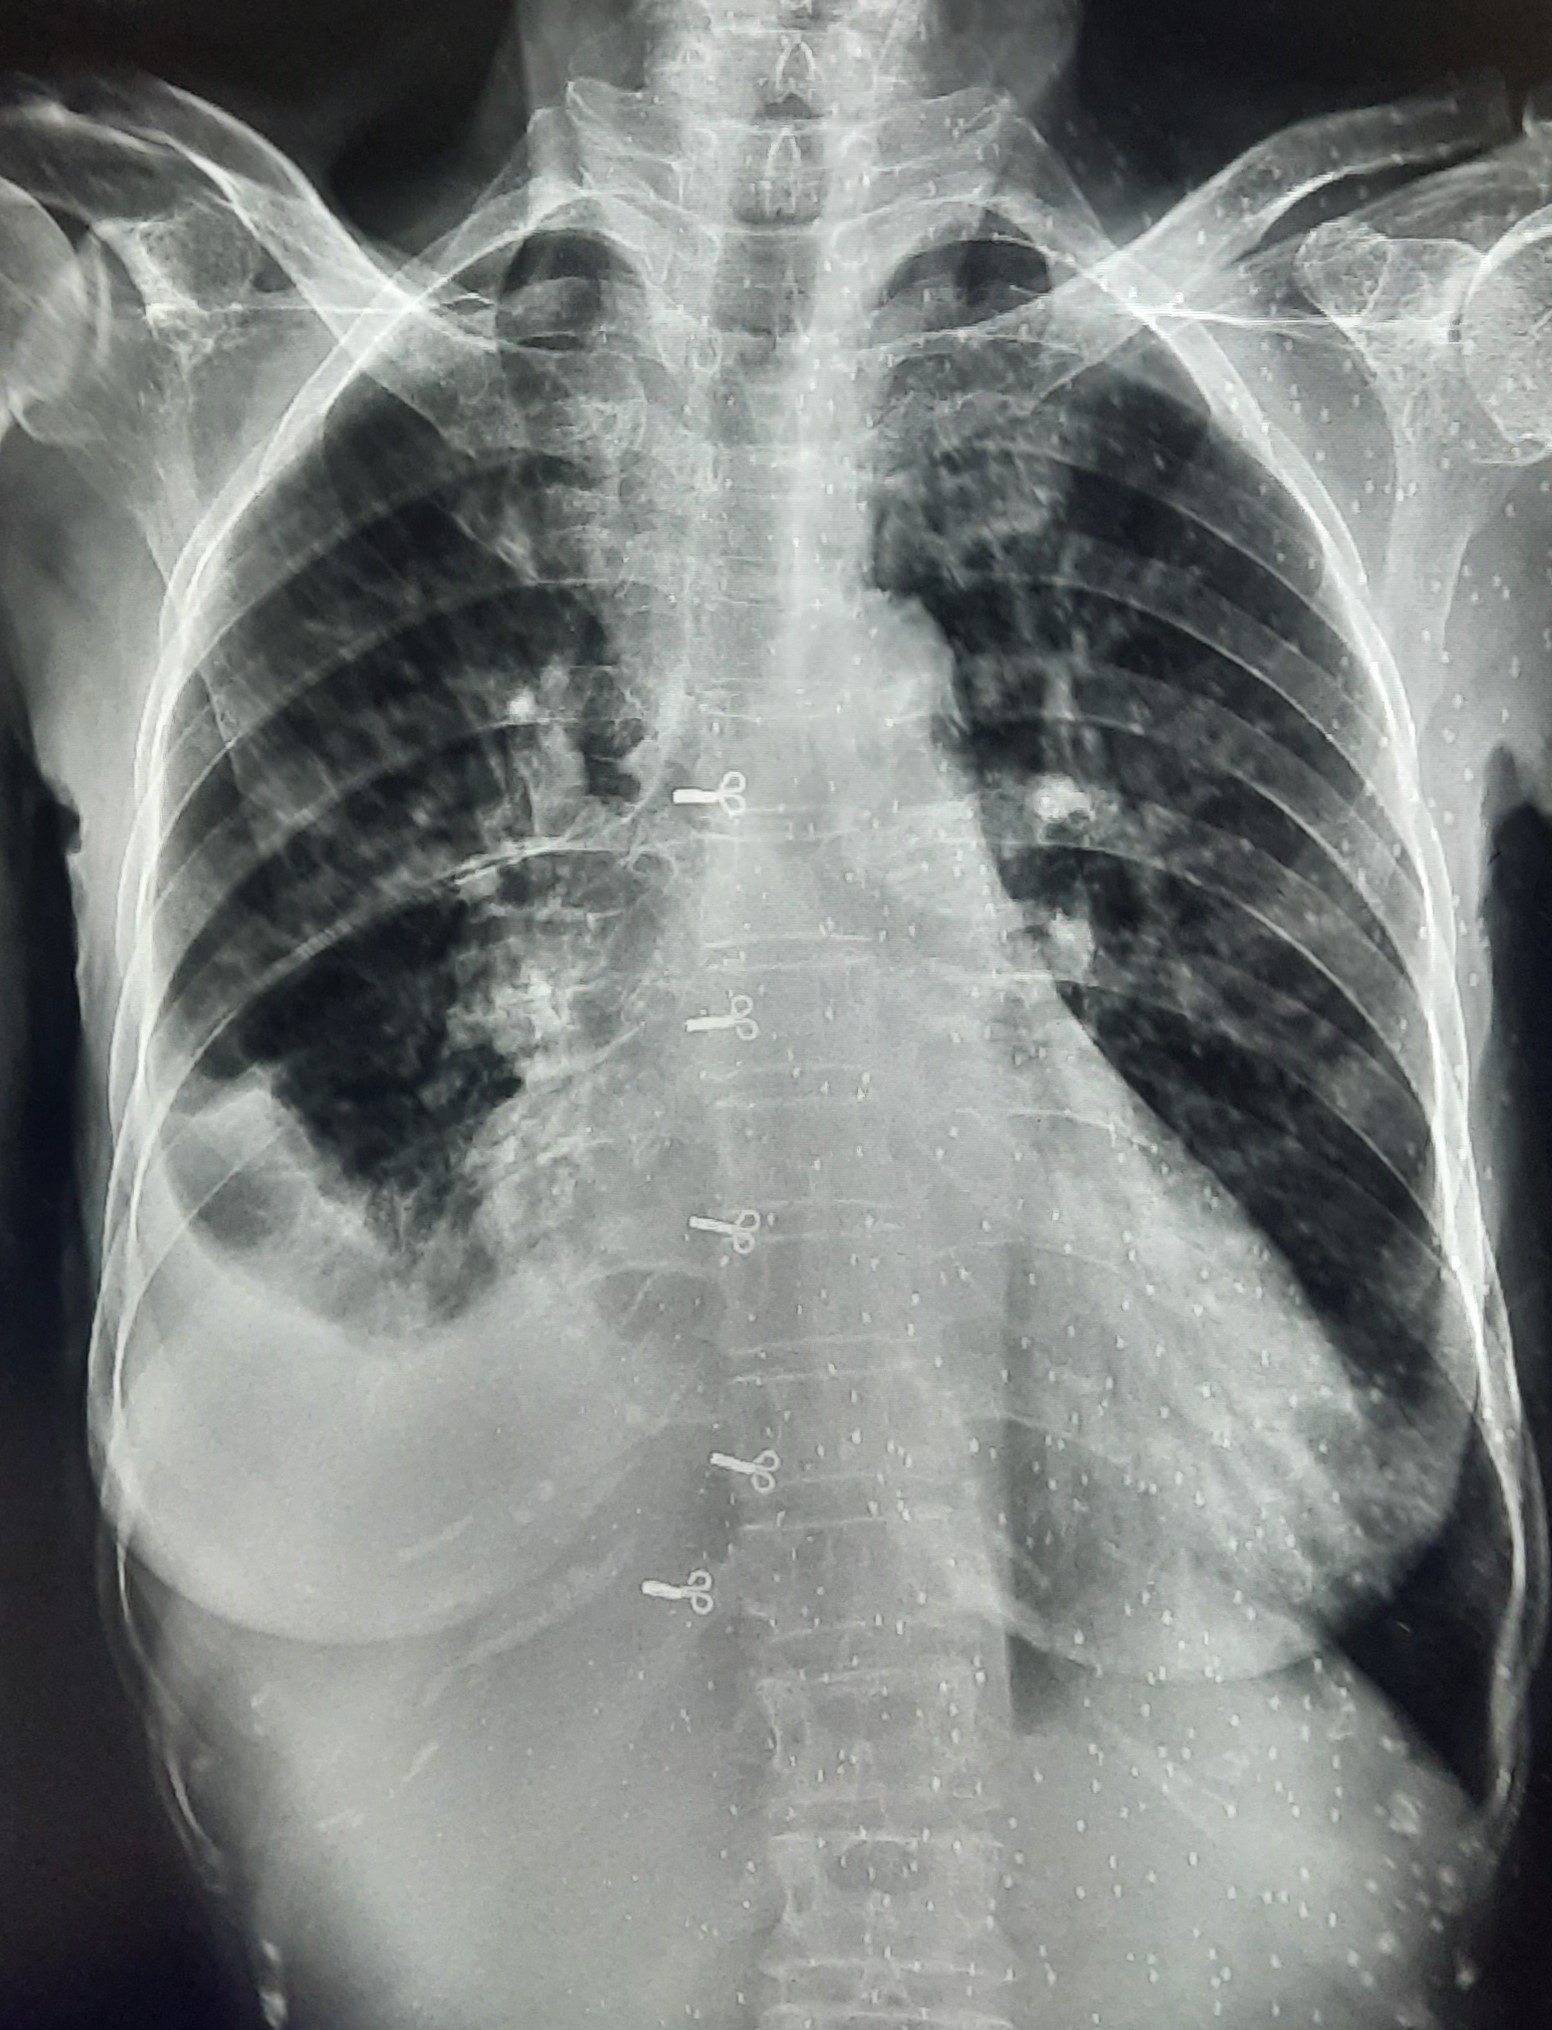

| 262 | IGGMC, Nagpur, Nagpur | P2 | 29-4210 | Mohamad Aslam | Consent taken on Paper | 35 Yrs. |

Provisional Diag : C/O Extra Pulmonary TB

Final Diag : FIBROSIS |

TB Case (Confirmed) | S/O RETICULAR OPACITIES NOTED IN RIGHT UPPER & MIDDLE ZONE/ QUERY FIBROSIS | Abnormality visible on x-ray |